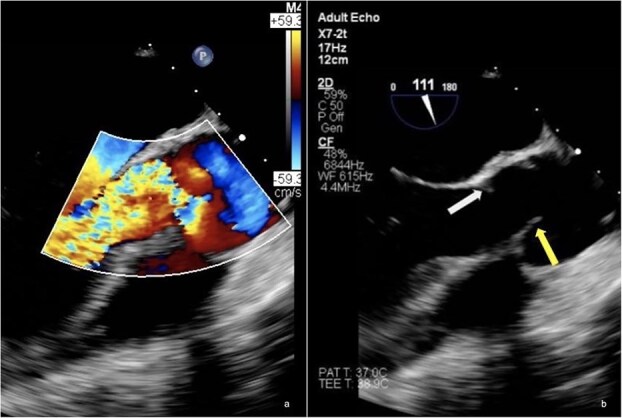

Cogan Syndrome (CS) is a rare autoimmune disease, complicated by a variety of cardiac manifestations. This case report represents the only documented case in the Republic of Cyprus. It describes the experience of a 23- year-old woman with CS who presented with newly diagnosed, severe aortic regurgitation (AR) and suspected endocarditis. The patient was initially treated successfully with a Ross procedure, but the recurrence of acute AR a few years later, led to the decision to treat her with a mechanical valve replacement, minimising complications and providing as permanent of a surgical solution as possible. This case demonstrates the importance of individualising treatment for such patients.